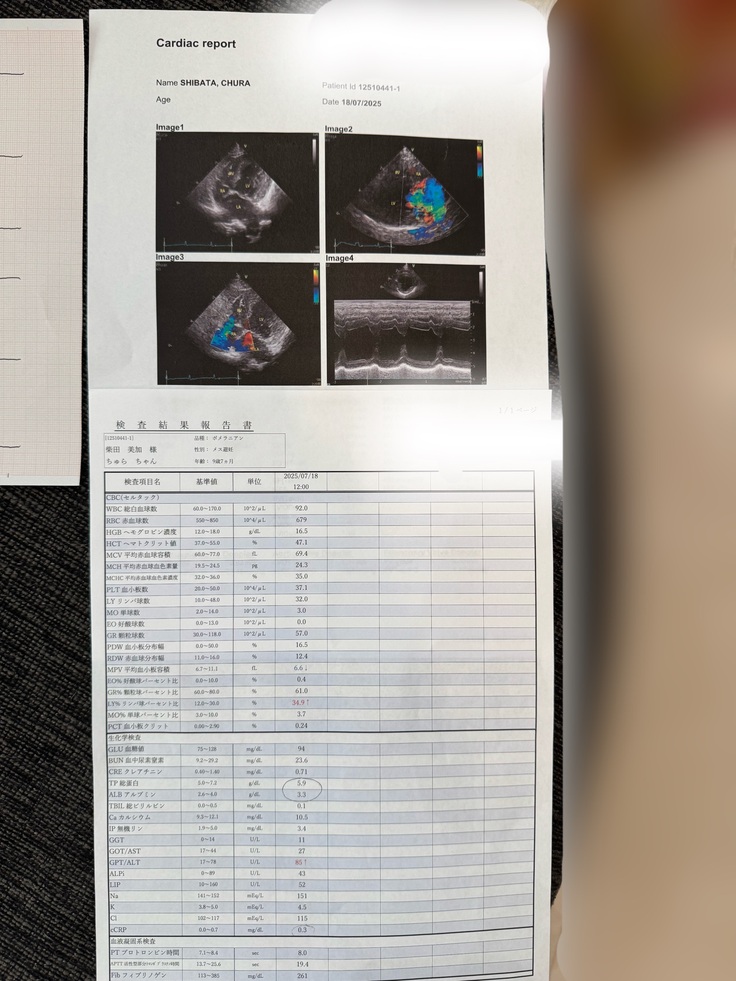

2025.7.18手術前の検査を行いました。

※すでに支払った治療費の明細になります。

この時のちゅらの心臓の状態から、薬の量をが、2/3錠から1錠に変更になりました。

さらに詳しく検査をしていただき、ここでかかりつけ医の先生の診断通りと、正式に『僧帽弁閉鎖不全症』という診断を受けました。

※診断書は、診療日の数日後に発行をお願いしたので、診療日と診断書の発行日は異なります。